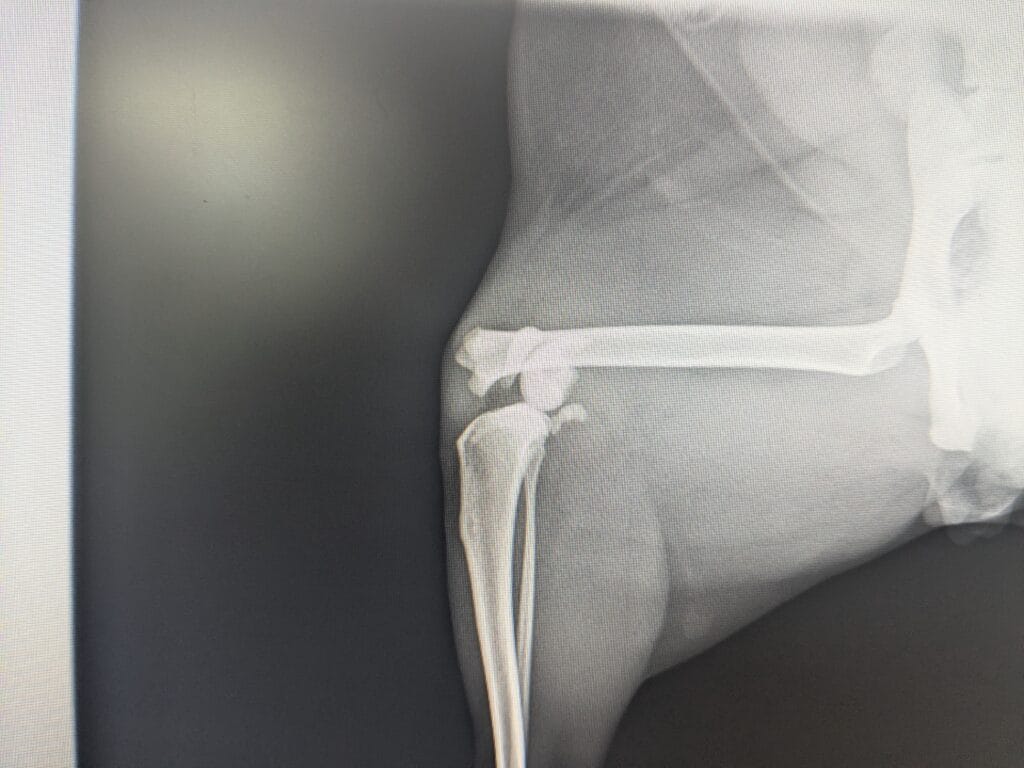

先ほど述べた分類でいくと、この骨折は「1型」となります。

私の人差し指のところに骨折線があります。画像は整復が終わった後の写真です。

通常は左右からピンを入れて終了となりますが、猫ちゃんは特に後肢の力が強いこと(=固定具が力に負けて折れやすい)、室内飼いにも関わらず骨折が起きてしまったことなどから固定強度を高めるために外側から追加でピンを1本入れています。